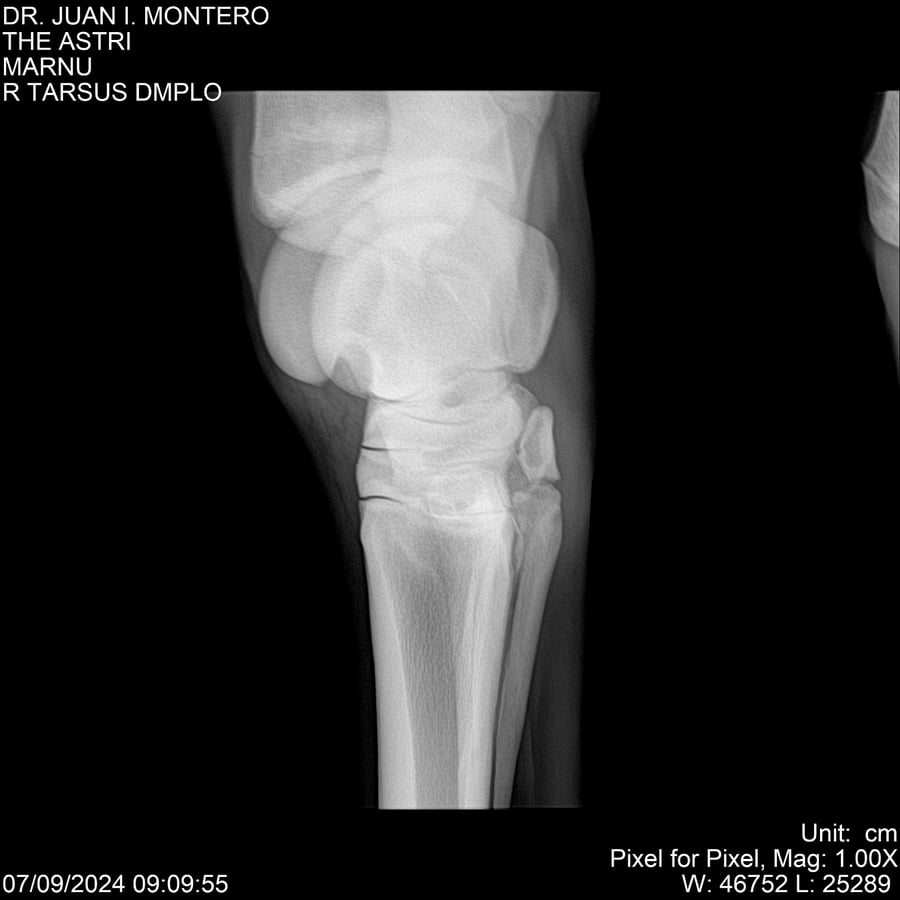

LOTE 10, THE ASTRI Lote Anterior Volver al remate Lote Siguiente Ficha Contacto Montevideo - Ficha del Lote Identificador: #282514 Categoría: Yeguarizos Montevideo - 60 Visualizaciones ClicData Contacto Empresa: Abelenda N. R., Walter Hugo Nombre*: Teléfono* : E-mail* : Mensaje Enviar Registrese gratis Este contenido Exclusivo está disponible sólo para usuarios registrados Ingresar